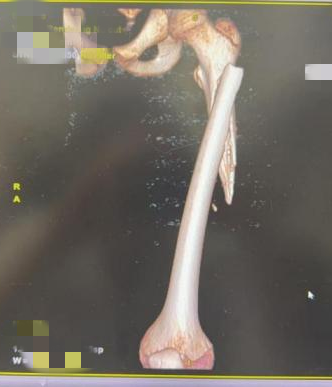

紧急送医后,当地医院的检查结果让一家人愣住:瑞瑞左侧股骨中断骨折,而且骨质密度普遍偏低。为了进一步治疗,瑞瑞很快被转往浙大儿院急诊创伤外科,经详细检查,医生确诊其为 “左侧股骨中上段骨折”,随后收治进骨科病房。

“儿童骨折常见,但12岁孩子轻轻一推就股骨骨折,尤其是从影像学上看,瑞瑞的骨质密度偏低,这可能是导致他轻微外力下就发生骨折的原因,这事儿不简单。” 接诊的浙大儿院骨科副主任陈建松副主任医师,当时就觉得这起骨折背后藏着蹊跷。

无论背后是否有进一步原因,当务之急是把骨折问题先解决!于是,陈建松副主任团队在为瑞瑞完善检查后,迅速实施了“左股骨骨折微创复位弹性钉固定术”,手术很顺利,瑞瑞的骨折部位得到固定。